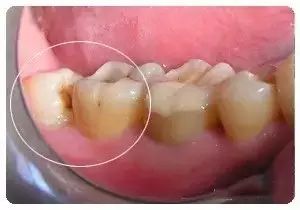

- Among those with erupted wisdom teeth, impaction and misalignment account for about 44%.

This can be seen very clearly on X-rays.

Due to poor positioning during eruption, wisdom teeth may be partially or fully covered by gum flaps. Being located on the innermost part of the mouth, they are difficult to clean while brushing, making it easy for food particles to become trapped between the teeth and leading to bacterial growth and inflammation. The pain intensifies during activities such as chewing, swallowing, and opening the mouth, and may even spread to infect other teeth. In the later stages of pericoronitis, symptoms may include halitosis, thick tongue coating, and pus discharge around the wisdom teeth. In severe cases, half of the face may become swollen, making it difficult to eat. Other accompanying symptoms may include fever, headache, constipation, and lymph node enlargement.